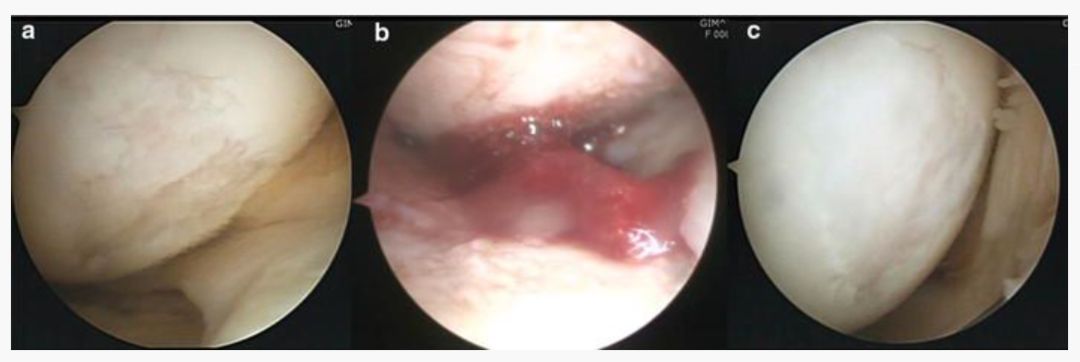

研究结果:大多数患者在最终随访中的所有结果测量均有显著改善。在第二次关节镜检查中,14个(总共16个)的关节软骨没有退化,只有5例患者的Kellgren-Lawrence评分恶化。

上图a为治疗前关节镜检查结果,可以看出软骨存在缺损。图b为脂肪间充质干细胞联合PRP治疗,图c为治疗后结果,软骨得到了修复。